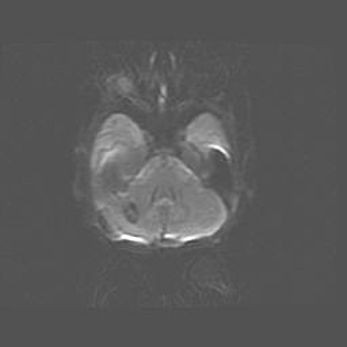

Лейкомаляция с кистозно-глиозной дегенерацией головного мозга.

Возраст: 2 месяца 25 дней

Вес: 6400 г

Окружность головы: 40 см

Срок гестации: 41 неделя

Лейкомаляцию относят к ишемически-гипоксическим повреждениям головного мозга, диагностируемым у новорожденных. При лейкомаляции в головном мозге обнаруживают очаги некроза, возникшие после тяжелой гипоксии и нарушения кровотока. В процессе морфогенеза очаги проходят три стадии: 1) развития некроза, 2) резорбции и 3) формирования глиозного рубца или кисты. Перивентрикулярная лейкомаляция (ПЛ) встречается примерно в 12% случаев среди новорожденных, обычно – у недоношенных детей, причем, частота ее зависит от массы, с которой младенец появился на свет. Наибольшее число малышей страдает лейкомаляцией, если масса при рождении 1500-2500 г.